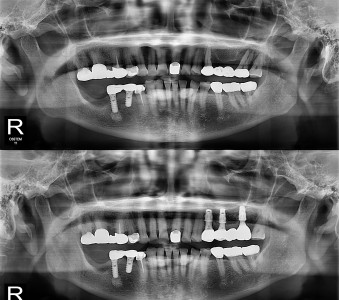

오스템 임플란트 프리미엄 BA 등급 사용

같은 오스템이라도 등급이 다릅니다. 더 빠른 골유착을 위해 프리미엄 등급을 사용합니다.

정확성 높은 치료의 시작 디지털 정밀진단 시스템

3D 디지털 데이터 기반으로 정확성 높고 정교한 치료가 가능합니다.

결과로 증명합니다.

국제모아치과의

실제 임상 증례